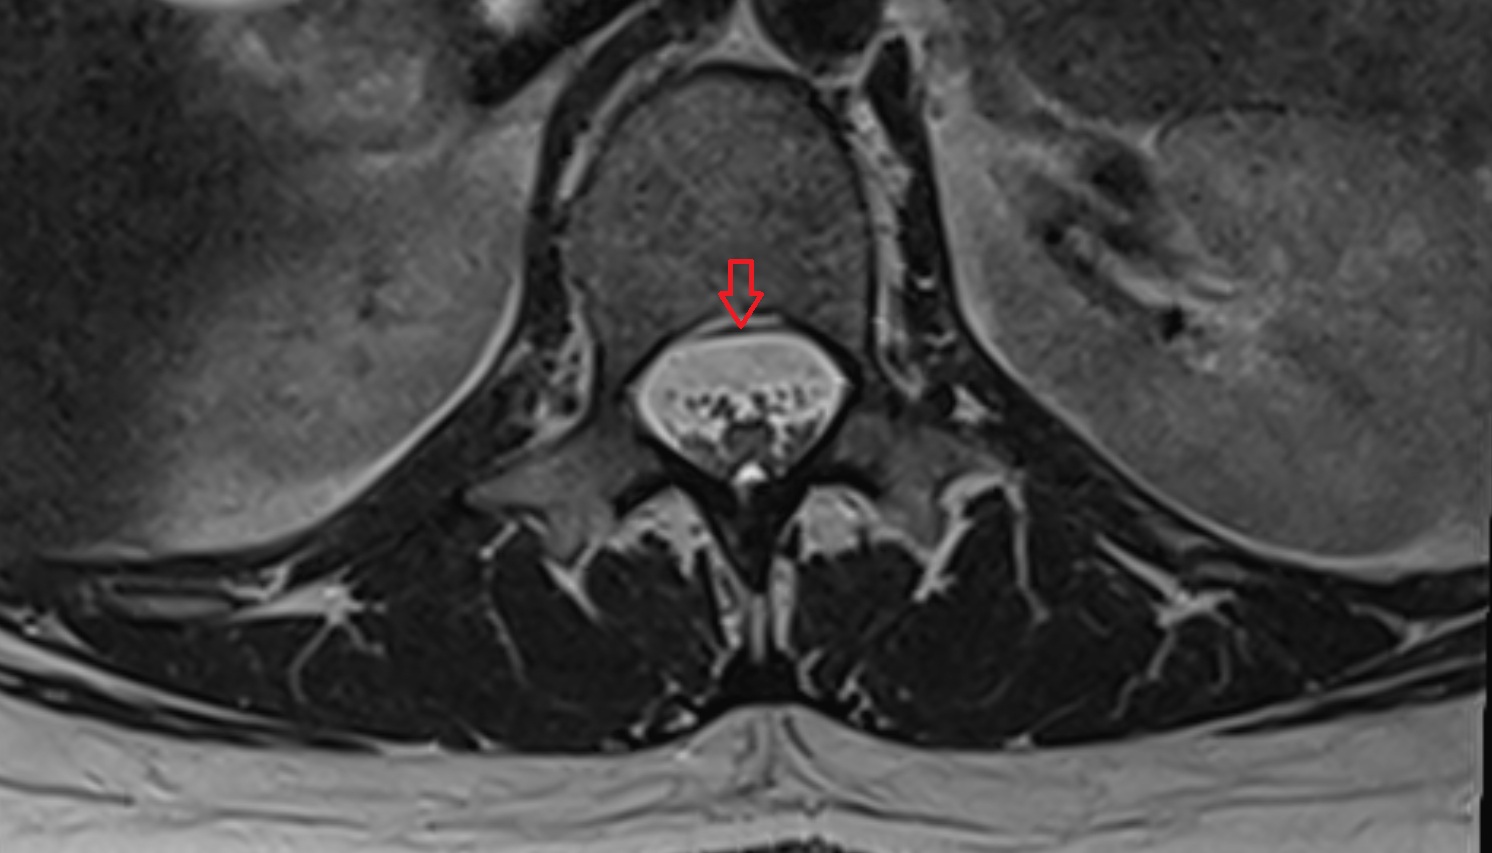

- Spinal cord

- subarachnoid space of spinal cord

- Cauda equina

- Conus medullaris